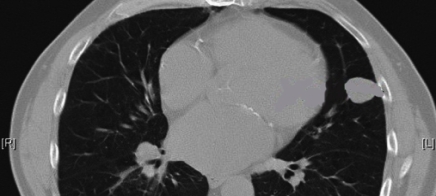

Kurs 1: Lunge

Autor: Achenbach J, Wagner T, Harth M, Jacobi V

Vielschichtige Entscheidungen im zeitlichen Verlauf bei sich verändernden Pathologien: Treffen Sie die sinnvollsten Entscheidungen im zeitlichen Ablauf der Anamnese, Diagnostik und Therapie dieses Krankheitsverlaufes.